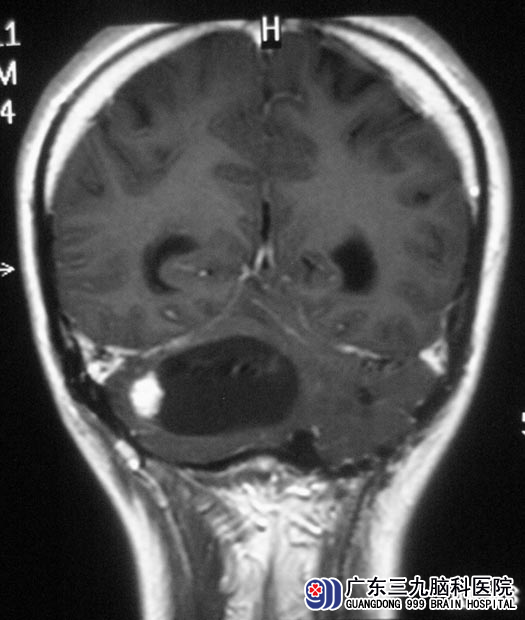

梁先生一周前出现头晕,可自行缓解。症状反复出现,并伴有头痛、走路不稳,为求放心去医院检查。头颅CT提示:右侧小脑占位性病变,广东三九脑科医院MR提示肿瘤大小约5.94cm×3.81cm×3.69cm,初步考虑为血管母细胞瘤。

综合神经外科鲁明主任主刀,在全麻下行后正中入路右侧小脑半球血管母细胞瘤切除术,术中见肿瘤呈囊实性,囊液呈草绿色,沿外侧切除实性部分,肿瘤呈粉红色血管团,质软,血供丰富,在显微镜下予肿瘤切除,手术顺利。术后,梁先生走路较术前好转,康复出院。术后病理结果为:血管母细胞瘤。